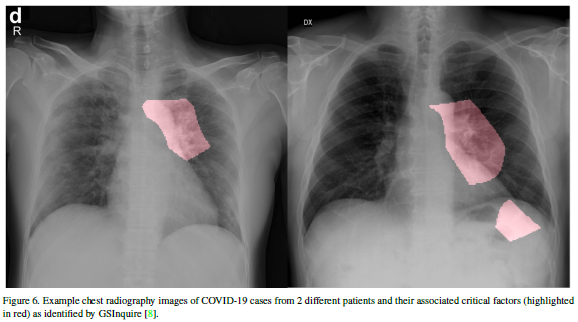

这篇论文开源了一个用于从胸部X射线图像中检测COVID-19病例而设计的深度卷积神经网络,即COVID-Net。用于训练COVID-Net的胸部放射线图像数据集名为COVIDx,包含了来自两个开放数据库的2839例患者的5941个由后向前胸部放射线图像。这篇论文还分析了COVID-Net如何使用可解释性方法做出预测,以期深入了解与COVID病例相关的关键因素,从而可以帮助临床医生进行更好的筛查。开放的数据和代码有助于进一步开发高精度和实用的深度学习解决方案,用于检测COVID-19病例。